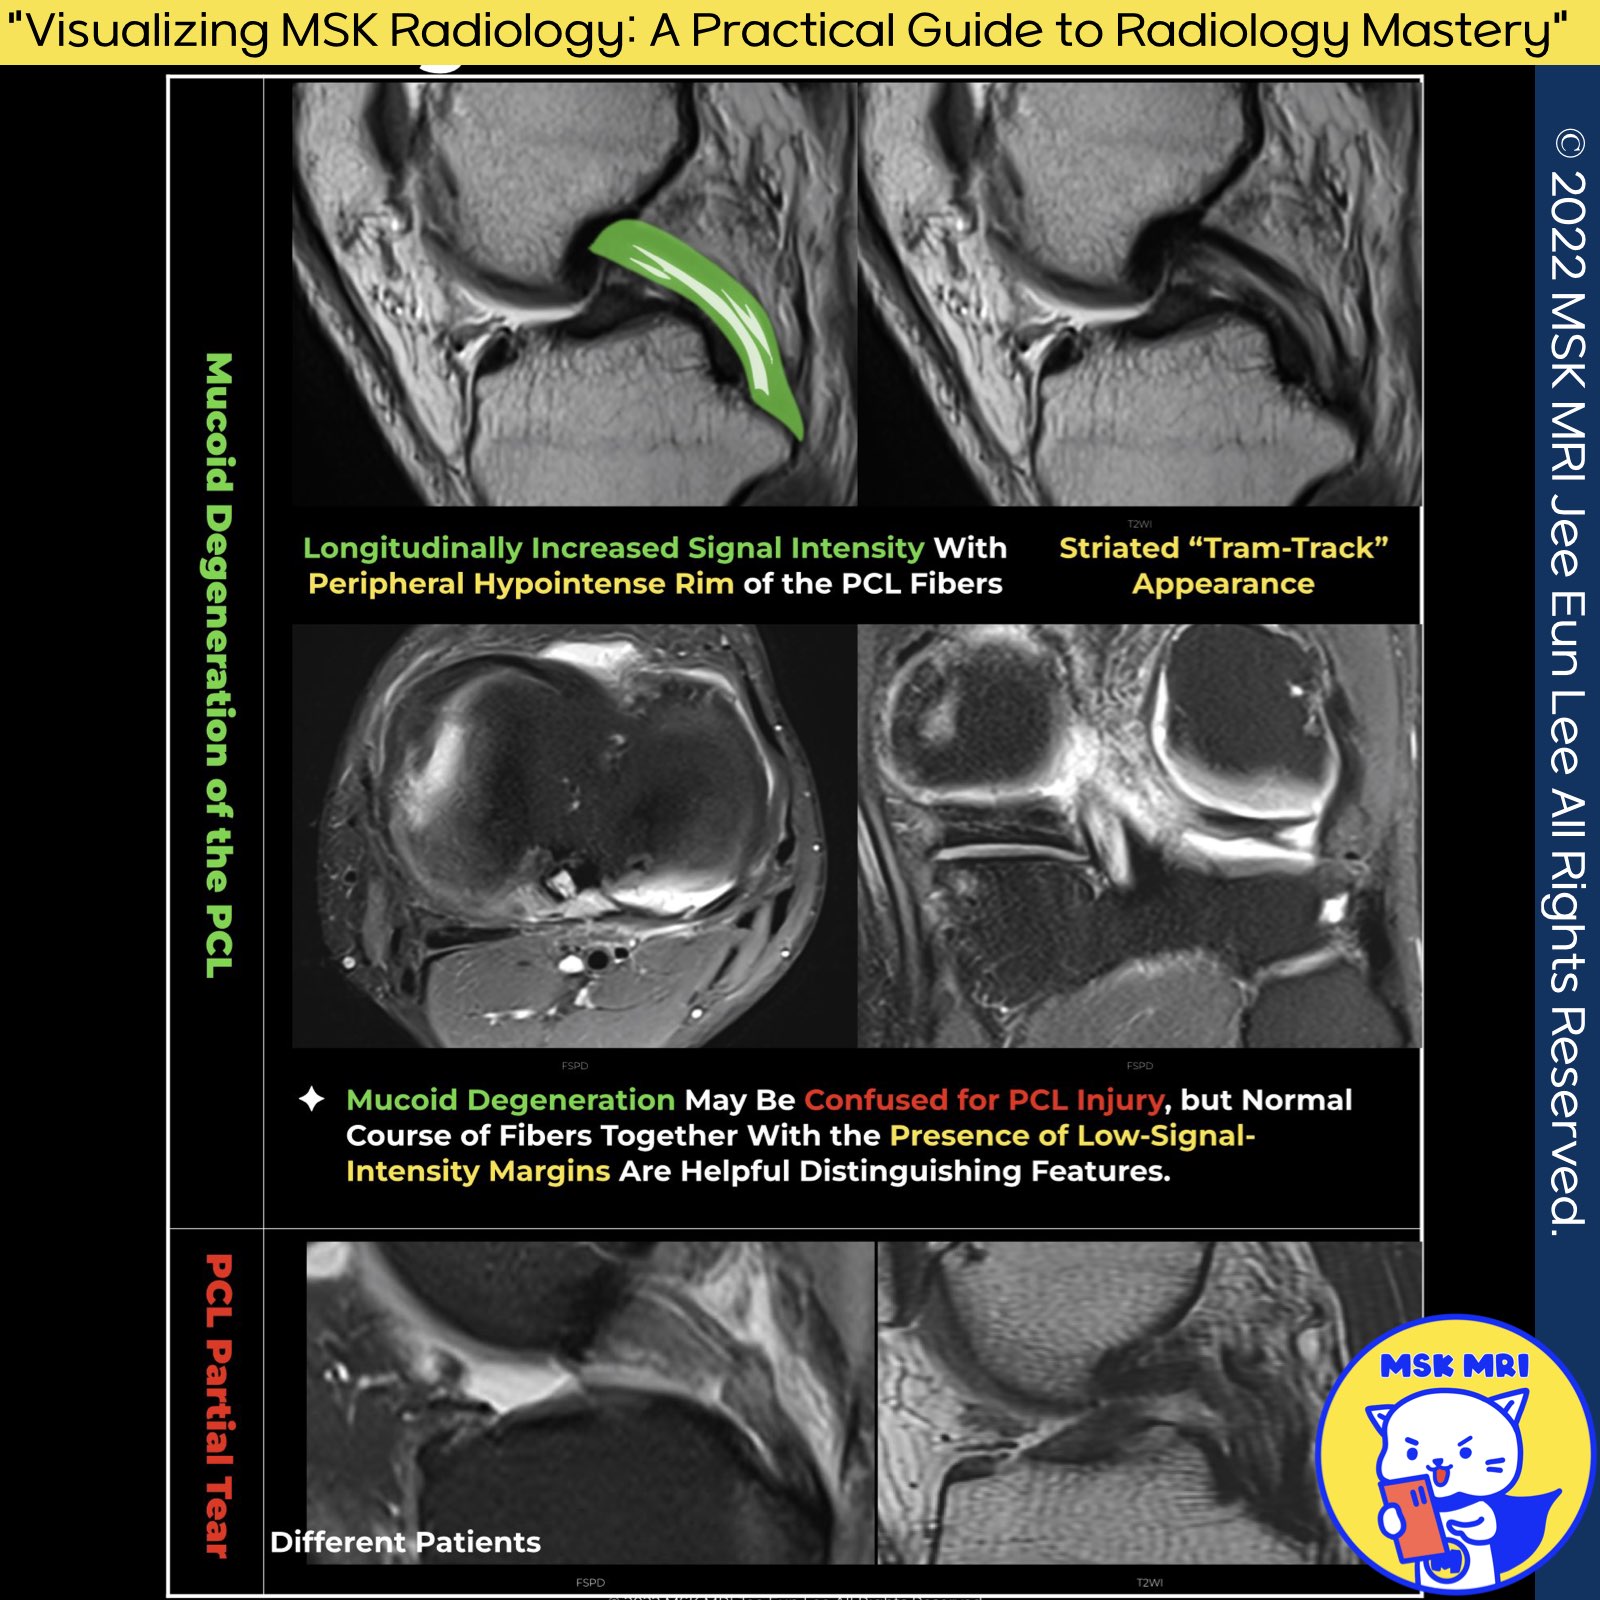

1️⃣ Mucoid Degeneration of the PCL

- Diagnosis Criteria: Mucoid degeneration of the PCL should be diagnosed when the ligament is intact and thickened, with increased signal intensity on fluid-sensitive sequences. This is especially relevant in patients with no history of trauma or knee injury and no clinical signs of ligamentous instability.

- Characteristic Appearance: Intrasubstance mucoid degeneration of the PCL can demonstrate a striated “tram-track” appearance with thickening that might mimic a tear.

2️⃣ Mucoid Degeneration vs. Partial Tear

- Differentiation: Mucoid degeneration may be confused for a PCL injury, but the normal course of fibers along with the presence of low-signal-intensity margins are key distinguishing features.

- Key Observation: In intrasubstance mucoid degeneration of the PCL, which results in a “tram-track” appearance, the abnormal signal should not violate the ligament's margins.